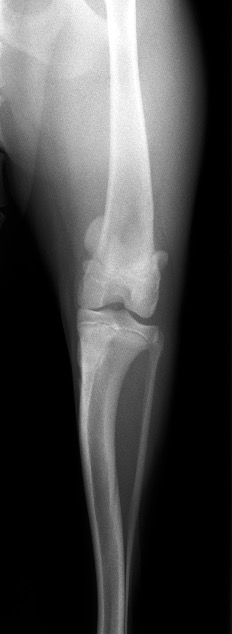

次の2枚の写真はパテラアルタのある今回の子と正常の子の膝関節と膝蓋骨の位置を示したものです。

正常膝関節